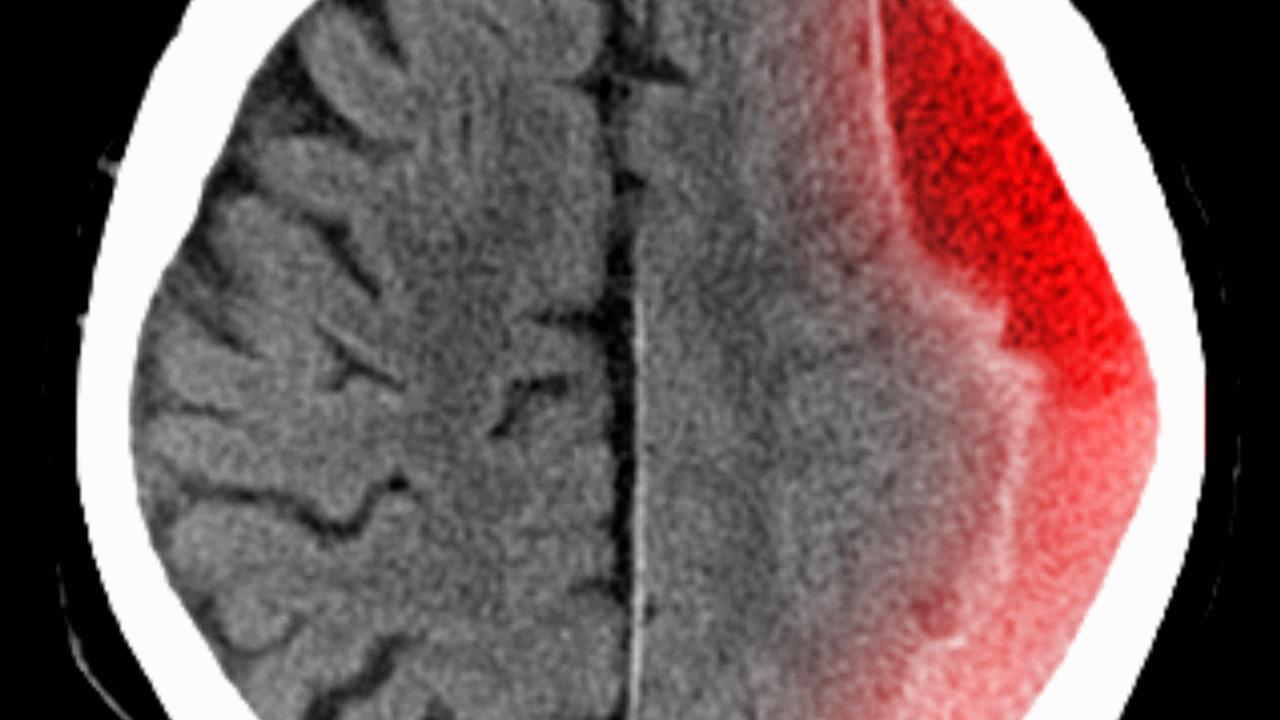

brain scan showing an injury